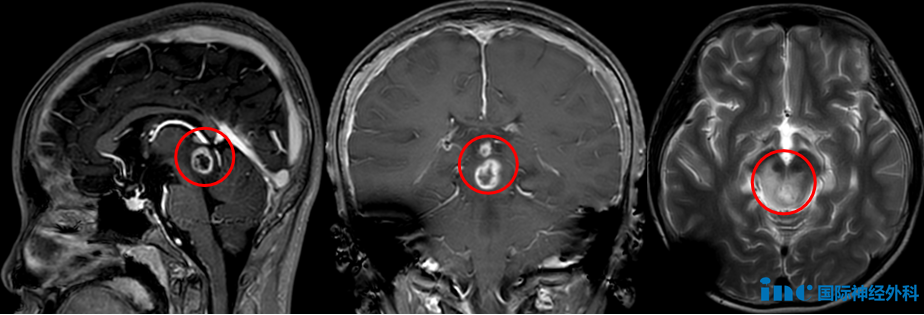

第一个孩子,12岁的小泰,喝水时总会有水从左侧嘴角流出,笑起来时面部歪斜,而且右眼无法完全闭合。检查发现一个“肿瘤”。悄无声息地潜入,在小泰的生命中枢——脑干中脑定居下来。初时,它似乎并没有恐怖至极,且体积尚小。肿瘤虽然造成脑积水,但是通过脑室腹腔分流术得到缓解,这让家人暂且松了一口气。

然而,在这小小的头颅之内,如果肿瘤逐渐长大呢?手术风险太大了,他们选择了伽马刀。没想到,它居然逃过了伽马刀,残留下的部分正缓慢生长、伺机而动。而且,肿瘤周围的正常组织已经发生坏死,必须“快刀斩乱麻”!

在这关键时刻,尤其需要“亡羊补牢”的决心与精湛技艺。所幸的是,一位深谙如何应对这些潜伏在儿童大脑中的“怪兽”的巴教授适时来华。点击阅读:开颅术后3天,这个打败脑干胶质瘤的小赢家中气十足说拜拜!